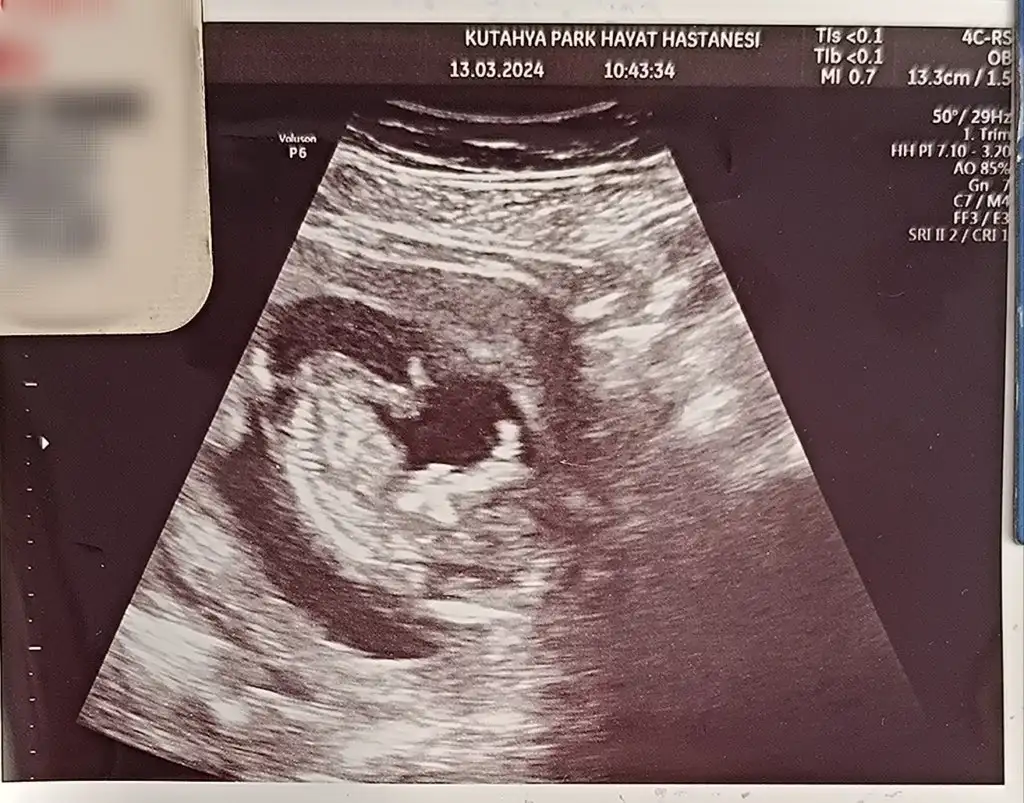

Çektiği fotoğraflar da bu kızlar.1 foto bacak mı kızlar

Bak canım bu benimki videodan kestiğim için bulanık ama aynı gibi görüntülerimiz 😄 yuvarlağa aldığım pipi

Hayır, benim bebiş utangaç biri sanırım, ısrarla göstermedi ve uyudu 😁 eğer gösterirse haftaya öğrenicez inşallah 🤗 tahmin ederim derseniz 13+4 ten ultrason görüntüsü 😁